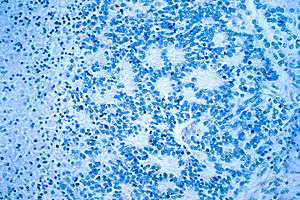

Microscopic view of a typical neuroblastoma with rosette formation | |

On microscopy, the tumor cells are typically described as small, round and blue, and rosette patterns (Homer Wright rosettes) may be seen. Homer Wright rosettes are tumor cells around the neuropil, not to be confused with pseudorosettes, which are tumor cells around a blood vessel.[25] They are also distinct from the pseudorosettes of an ependymoma which consist of tumor cells with glial fibrillary acidic protein (GFAP)–positive processes tapering off toward a blood vessel (thus a combination of the two).[26] A variety of immunohistochemical stains are used by pathologists to distinguish neuroblastomas from histological mimics, such as rhabdomyosarcoma, Ewing's sarcoma, lymphoma and Wilms' tumor.[27]

Neuroblastoma is one of the peripheral neuroblastic tumors (pNTs) that have similar origins and show a wide pattern of differentiation ranging from benign ganglioneuroma to stroma-rich ganglioneuroblastoma with neuroblastic cells intermixed or in nodules, to highly malignant neuroblastoma. This distinction in the pre-treatment tumor pathology is an important prognostic factor, along with age and mitosis-karyorrhexis index (MKI). This pathology classification system (the Shimada system) describes "favorable" and "unfavorable" tumors by the International Neuroblastoma Pathology Committee (INPC) which was established in 1999 and revised in 2003.[28]

In 1864 German physician Rudolf Virchow was the first to describe an abdominal tumor in a child as a "glioma". The characteristics of tumors from the sympathetic nervous system and the adrenal medulla were then noted in 1891 by German pathologist Felix Marchand.[66][67] In 1901 the distinctive presentation of stage 4S in infants (liver but no bone metastases) was described by William Pepper. In 1910 James Homer Wright understood the tumor to originate from primitive neural cells, and named it neuroblastoma. He also noted the circular clumps of cells in bone marrow samples which are now termed "Homer Wright rosettes". Of note, "Homer-Wright" with a hyphen is grammatically incorrect, as the eponym refers to just Dr. Wright.[68]